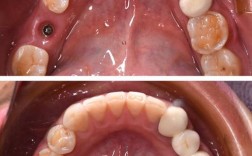

- 植入种植体:通过手术将钛合金种植体植入牙槽骨。

- 骨结合期:等待种植体与牙槽骨牢固结合,通常需要3-6个月。

- 安装基台和牙冠:骨结合完成后,安装上部修复体。

骨结合期是种植牙成功的关键,也是患者最常疑惑的部分。